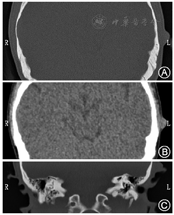

患者女性,26岁,因"左耳肿痛4个月余"于2018年11月4日来广州市增城区人民医院耳鼻喉科就诊并收入院。患者4个月前无明显诱因出现左耳肿痛,无发热,无耳流脓、听力下降、耳鸣,无眼睑闭合不全,无眩晕,曾就诊予头孢类药物治疗,耳痛症状好转,耳廓肿胀无法消退,近4个月来左耳肿胀隆起进行性加重,无伴疼痛,拟"左耳肿物性质待查"收入院。患者既往史无特殊,无疫区疫水及传染病接触史,否认肿瘤家族史。入院时专科体格检查:左耳廓背面、耳后沟前上方新生物,约1.0 cm×0.5 cm,表面光滑,边界清,质稍硬,活动度差,无明显压痛。新生物下方另见一孤立绿豆大小结节,表面光滑,性质同上,无压痛,耳廓表面皮肤未见破损及皮疹,余检查未见异常。入院后完善常规检查未见异常,颞骨薄层CT提示:左侧耳廓上方结节,边界尚清晰,无邻近组织侵犯表现(图1)。术前诊断为左耳肿物,于11月5日在局麻下行耳廓肿物切除,术中所见耳廓肿物边缘尚清晰,未见包膜包裹,与周围组织粘连,底部紧贴耳廓软骨,充分分离后完整切除肿物,耳廓软骨完整无破坏,分层缝合术腔加压包扎,肿物送病理检查。患者术后恢复情况良好,术后第2天出院。病理结果回报:(左耳廓肿物符合炎性肌纤维母细胞瘤(图2)。术后1周患者返院复诊见伤口愈合良好,局部拆线,告知患者病理结果并嘱其定期随诊。现患者术后随访14个月,无肿瘤复发表现,耳廓局部除轻微瘢痕形成外无明显异常。

IMT无特定临床表现,症状与肿瘤所在部位有关,单纯依靠临床表现容易漏诊[9]。IMT在影像学方面也缺乏特征性表现,常表现为浸润性生长,也可出现骨质增厚、破坏等类似恶性肿瘤特征。影像学检查可为IMT的定位、周围组织侵犯及血管包绕、制订治疗方案、疗效评估等方面提供参考依据,但由于受肿瘤发生部位、体积及疾病进程等因素影响,难以完全依靠影像学对IMT明确诊断并鉴别其他病变[10,15]。本例患者术前急性炎症症状已消退,但耳廓肿胀隆起仍有加重,CT平扫中可见耳廓软组织占位,体积与体格检查大致相符,肿物边界尚清晰,未见明显侵犯表现,术前综合考虑为良性病变,行手术完全切除。